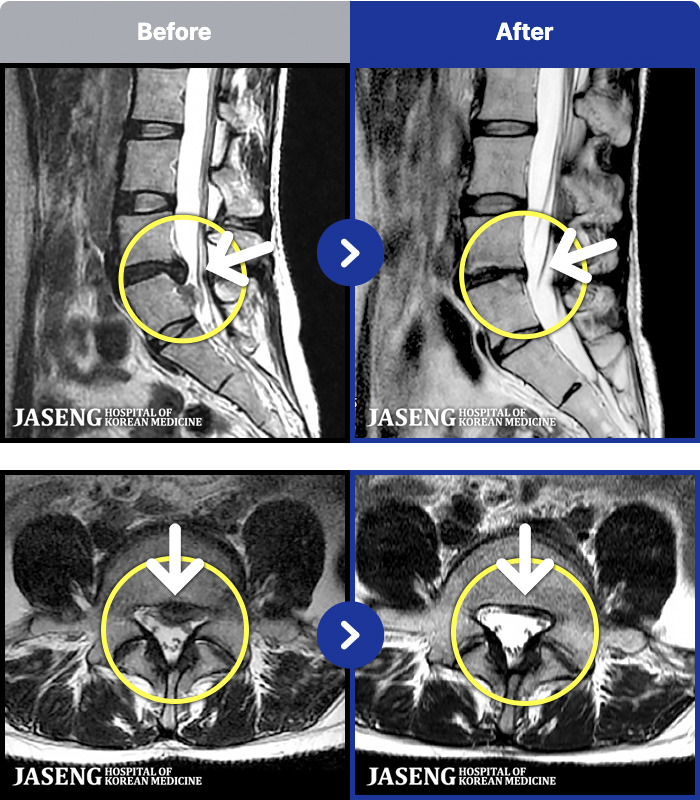

MRI ġ

1,240 MRI ũ ʸ Ȯϼ.